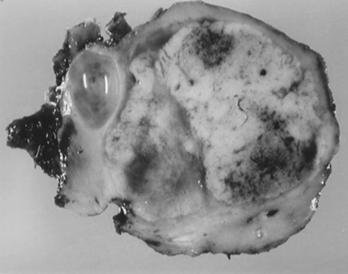

Exista forme de trecere progresiva de la chisturi simple unistratificate pana la neoplasm renal cu celule clare trecand prin toate formele intermediare atipice. Chisturile simple se dezvolta mai ales din tubii contorti distali, in timp ce neoplasmele si chisturile atipice provin din tubii contorti proximali. Majoritatea leziunilor chistice pure raman stabile, in timp ce chistele atipice si leziunile tumorale cresc in dimensiuni. [

Figura 9.5. Boala von Hippel Lindau- numeroase formatini tumorele solide si chistice. (aspect macroscopic si CT) adaptat dupa Bachir Taouli, Mehdi Ghouadni, Jean-Michel Corras, Pascal Hammel, Anne Couvelard, Stphane Richard and Valrie Vilgrain: Spectrum of Abdominal Imaging Findings in von Hippel-Lindau Disease, American Journal of Roentgenology

Frecventa leziunilor renale variaza de la 30-60%. Chisturile renale simple sunt cele mai frecvente. Neoplasmele observate la 35-38% din cazuri sunt adesea bilaterale, multifocale si de talie mica.